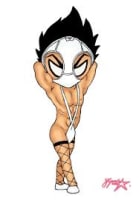

on m'a fait passer une pano (de mauvaise qualité... mais ça a peu d'importance dans ce cas), je voudrais savoir ce que ça vous inspire...

J'ai fait un petit zoom sur le secteur.